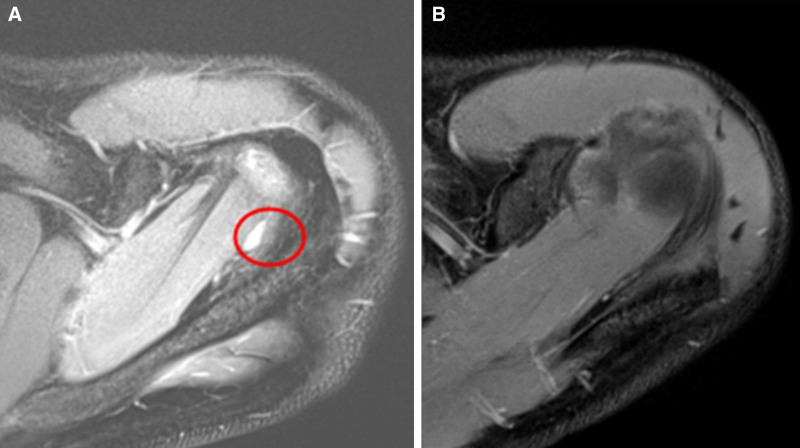

Management of Suprascapular Nerve Compression via Nonoperative Methods.

期刊介绍: Plastic and Reconstructive Surgery—Global Open is an open access, peer reviewed, international journal focusing on global plastic and reconstructive surgery.Plastic and Reconstructive Surgery—Global Open publishes on all areas of plastic and reconstructive surgery, including basic science/experimental studies pertinent to the field and also clinical articles on such topics as: breast reconstruction, head and neck surgery, pediatric and craniofacial surgery, hand and microsurgery, wound healing, and cosmetic and aesthetic surgery. Clinical studies, experimental articles, ideas and innovations, and techniques and case reports are all welcome article types. Manuscript submission is open to all surgeons, researchers, and other health care providers world-wide who wish to communicate their research results on topics related to plastic and reconstructive surgery. Furthermore, Plastic and Reconstructive Surgery—Global Open, a complimentary journal to Plastic and Reconstructive Surgery, provides an open access venue for the publication of those research studies sponsored by private and public funding agencies that require open access publication of study results. Its mission is to disseminate high quality, peer reviewed research in plastic and reconstructive surgery to the widest possible global audience, through an open access platform. As an open access journal, Plastic and Reconstructive Surgery—Global Open offers its content for free to any viewer. Authors of articles retain their copyright to the materials published. Additionally, Plastic and Reconstructive Surgery—Global Open provides rapid review and publication of accepted papers.